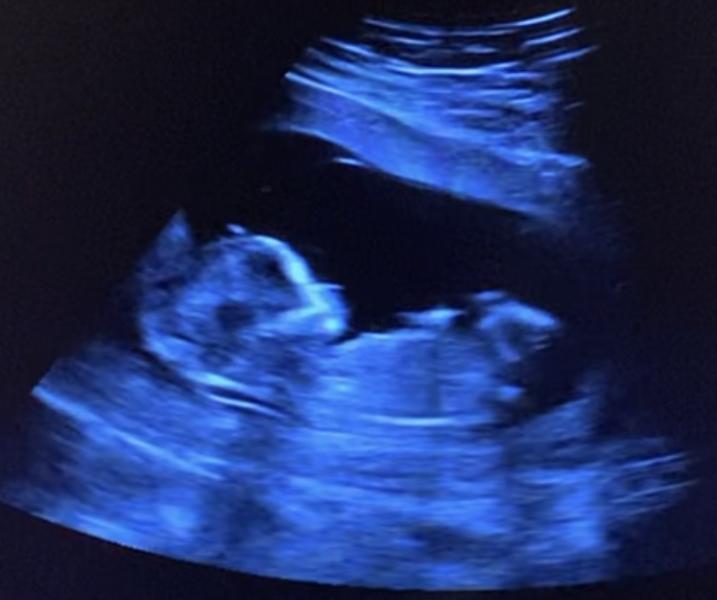

Каждый тревожный поход на узи успокаивала мамку идеальными показателями, на день-два больше графиков и таблиц! Нашлась под доплером на 11 неделе, наверное устала, что ее носят на узи раз в неделю😁

Моя прекрасная и чудесная дочь, жду в октябре ⏰💕